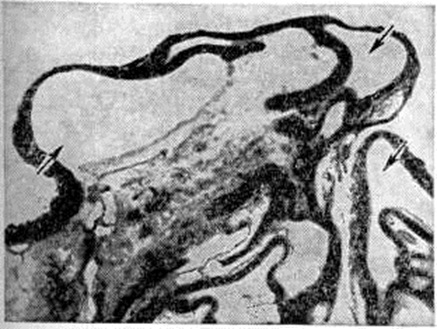

Патологическая анатомия. Различают так называемый мягкую стадию, или лимфедему, которая соответствует наличию выраженного, сначала преходящего, а затем стойкого отёка, смешанную, или промежуточную, стадию, когда фибредема локализуется лишь на периферии конечности, а в проксимальной её части ещё имеет место лимфедема, и твёрдую стадию, или фибредему, которая соответствует развитию тотального фиброза тканей. В начальной стадии Слоновость поражённый орган увеличен в объёме за счёт отёка. Кожа остаётся гладкой, без трофических изменений. Гистологически отмечается отёк и умеренный фиброз подкожной клетчатки, в которой обнаруживаются расширенные лимфатических, сосуды. В стадии хронический лимфедемы поражённый орган (особенно нижние конечности) резко увеличивается в объёме, деформируется, кожа нависает складками, утолщается, появляются трещины, язвы, наблюдаются папилломатозные разрастания. В поверхностных лимфатических, сосудах, а нередко и в глубоких лимфатических, коллекторах обнаруживаются лимфангиит и перилимфангиит, продуктивные облитерирующие воспалительные процессы — подострый и хронический эндолимфангиит (рисунок 1, а), гипертрофия (рисунок 1, б), склероз и гиалиноз стенок и клапанов лимфатических, сосудов и другие В лимфатических, сосудах могут быть изменения и без признаков воспаления, например, облитерирующая и дистрофическая лимфангиопатия, лимфангиэктазия (смотри полный свод знаний). Как следствие нарушения лимфооттока по магистральным коллекторам появляются признаки вторичной перестройки лимфатических, капилляров и сосудов кожи: рост и деформация лимфатических, капилляров, деформация, варикозное расширение и появление атипичных (спиралевидных) лимфатических сосудов, лимфангиэктазии кожи. В разных участках эпидермиса отмечаются атрофия (смотри полный свод знаний: Атрофия кожи), гиперкератоз (смотри полный свод знаний), акантоз (смотри полный свод знаний) паракератоз (смотри полный свод знаний) и вакуолизация эпителия. Атрофия эпидермиса особенно резко выражена при образовании лимфангиэктазий. При этом расширенные лимфатических, капилляры образуют в сосочковом слое дермы более или менее широкие полости, оказывающие давление на эпидермис, вызывая его атрофию (рисунок 2), местами до полного истончения и разрыва с истечением лимфы наружу (смотри полный свод знаний: Лимфорея). Лимфорея может быть продолжительной, особенно при наличии рефлюкса (смотри полный свод знаний), то есть ретроградного движения лимфы в связи с недостаточностью клапанов лимфатических, сосудов.

Рис. 1.

Микропрепараты глубоких лимфатических коллекторов кожи при вторичной слоновости: а — пролиферативный эндолимфангиит с поражением клапанов (указано стрелкой); окраска гематоксилин-эозином; ×120; б — гипертрофия стенки лимфатического сосуда (указано стрелкой); импрегнация по Гомори; ×120.